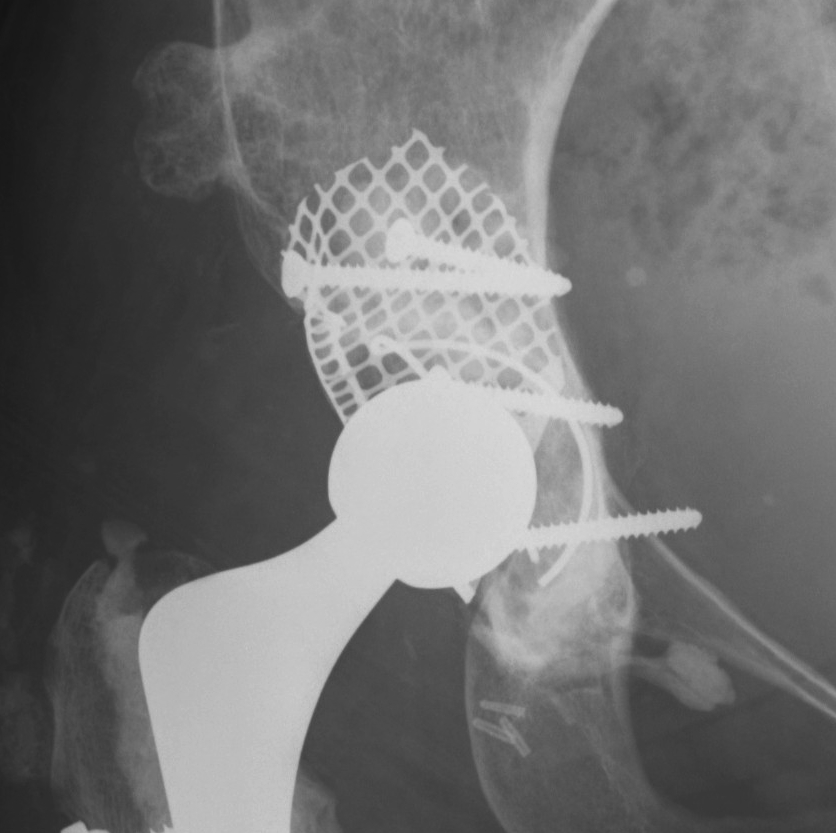

Option: Custom-made triflange components

CT guided model of pelvis

- custom made acetabular cage

- fits defect exactly

- flanges perfectly designed and not malleable to improve strength

- HA coated

- cement poly cup into it

Indications

- massive defects

Results

- 90% 4.5 year survival in complicated patients